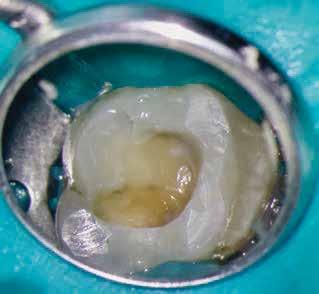

1. a–g. ábrák: A direkt pulpasapkázás lépései. Kiindulási bitewing-felvétel: A meglévő restaurátum közel helyezkedett el a pulpakamrához (a). Kiindulási periapicalis felvétel: Nincs periapicalis elváltozás fennállására utaló jel (b). A pulpaexpozíció (c). A vérzéscsillapítás céljából 20 másodpercen keresztül steril vattagombóccal történő kompressziót követően látható pulpaseb (d). A pulpasapkázás céljából behelyezett anyag, a széli részek tisztázása előtt készült felvétel (e). A röntgenárnyékot nem adó ideiglenes tömés behelyezése után készült felvétel (f). Az első ülés végén a röntgenárnyékot nem adó ideiglenes töméssel ellátott fogról készített röntgenfelvétel (g).

A diagnózisunk reverzibilis pulpitis volt. Periapicalis elváltozás jelenlétét nem vélelmeztük. A fogban lévő amalgámtömés eltávolítása során körülbelül egy 3 mm átmérőjű pulpaseb keletkezett a buccalis pulpaszarvnak megfelelően (1. a–g. ábrák) Mivel nem tapasztaltunk jelentős vérzést, és a diagnózisunk reverzibils pulpitis volt, ezért a direkt pulpasapkázás elvégzése mellett döntöttünk.

A kavitást 2,5%-os nátrium-hipoklorit oldattal fertőtlenítettük, majd sűrű konzisztenciájú kalcium-szilikát alapú anyagot (CeraPutty, Meta Biomed) készítettünk elő a direkt pulpasapkázás elvégzéséhez. Az első kezelés végén röntgenárnyékot nem adó ideiglenes töméssel (NexTemp LC, Meta Biomed) zártuk

az üreget annak érdekében, hogy a direkt pulpasapkázásra használt anyag megfelelő pozícióját radiológiailag ellenőrizni tudjuk. A második ülés során kompozit tömőanyagból (Ezfil, Meta Biomed) direkt adhezív restaurátumot készítettünk.

A kezelést követően a beteg tünetmentes volt. A kérdéses fog a kontrollvizsgálatok során végzett szenzibilitástesztekre fiziológiás reakciókat adott. A hat hónapos kontroll alkalmával készített röntgenfelvételen a sérülésnek megfelelően széles dentinhidat észleltünk (2. ábra). A restaurátum a hároméves kontroll során is megfelelőnek bizonyult (3. ábra)